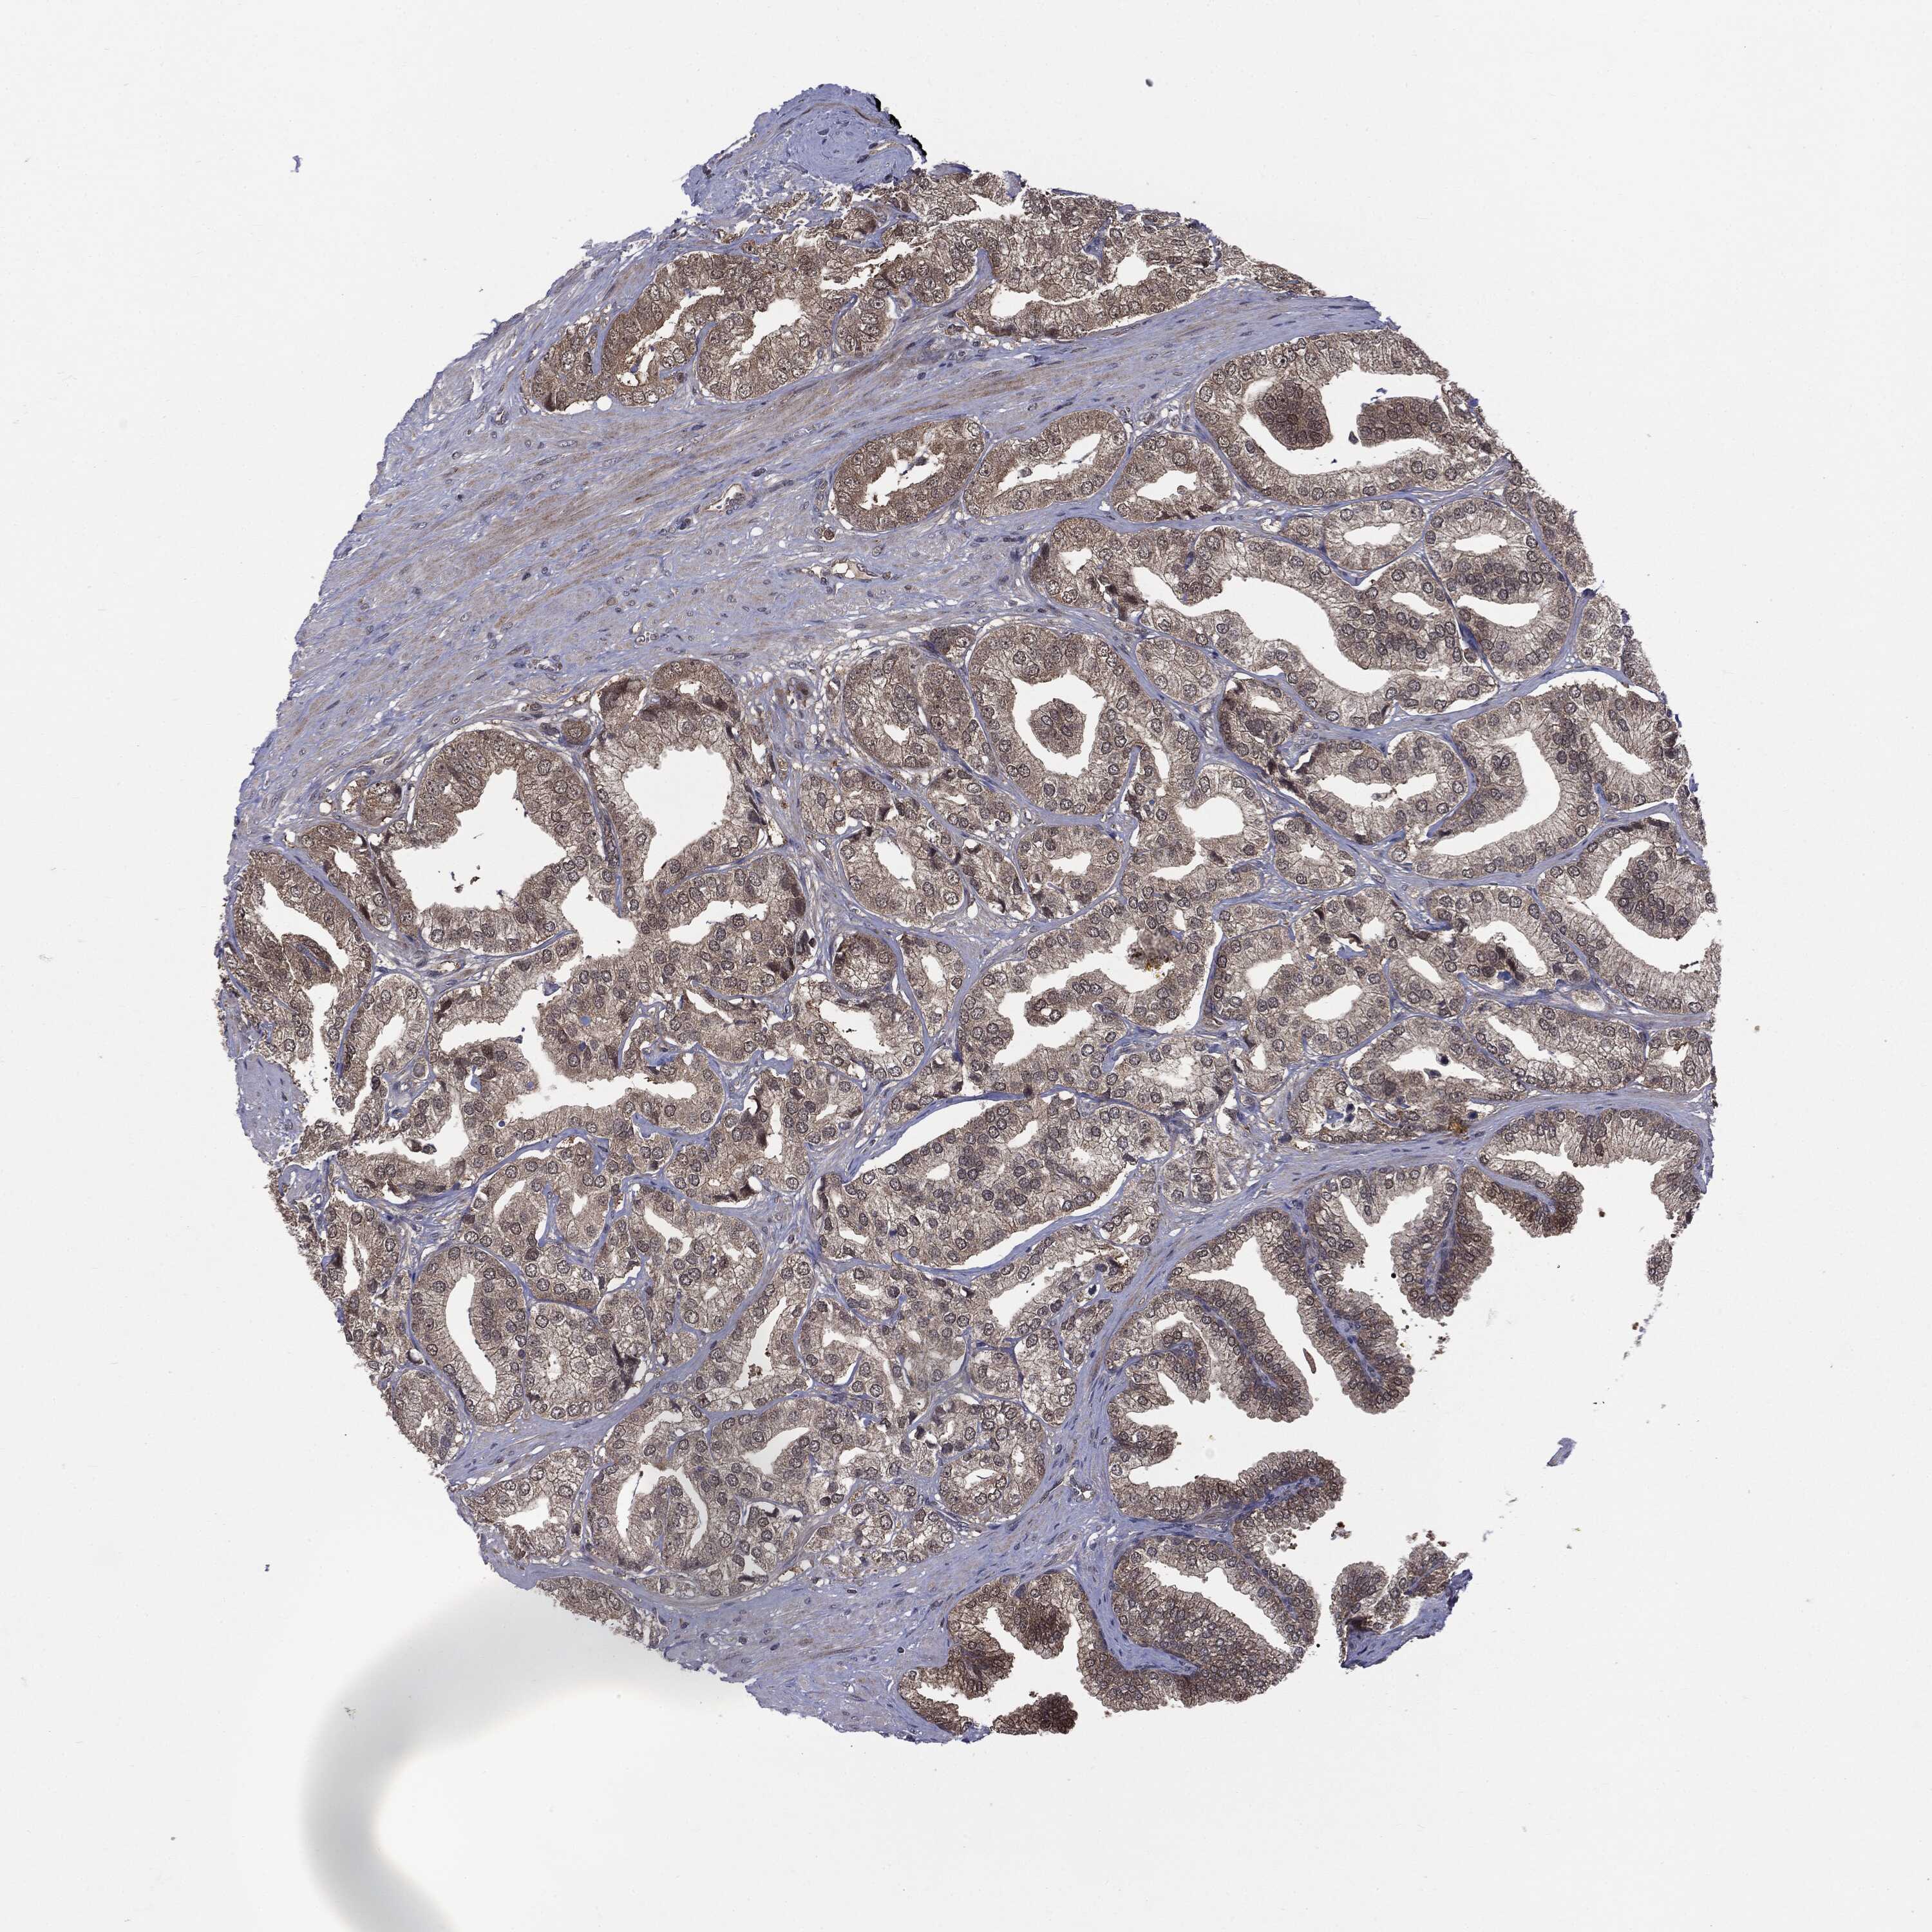

PROSTATE CANCER - Protein expressioni

A mouse-over function shows sample information and annotation data. Click on an image to view it in a full screen mode. Samples can be filtered based on level of antibody staining by selecting one or several of the following categories: high, medium, low and not detected. The assay and annotation is described here.

Note that samples used for immunohistochemistry by the Human Protein Atlas do not correspond to samples in the TCGA dataset.

Antibody stainingi

Antibody staining in the annotated cell types in the current human tissue is reported as not detected, low, medium, or high, based on conventional immunohistochemistry profiling in selected tissues. This score is based on the combination of the staining intensity and fraction of stained cells.

Each image is clickable and will lead to virtual microscopy that enables deeper exploration of all samples and also displays staining intensity scores, fraction scores and subcellular localization as well as patient and tissue information for each sample.

Adenocarcinoma, Low grade

Adenocarcinoma, High grade

Adenocarcinoma, NOS

Adenocarcinoma, Medium grade